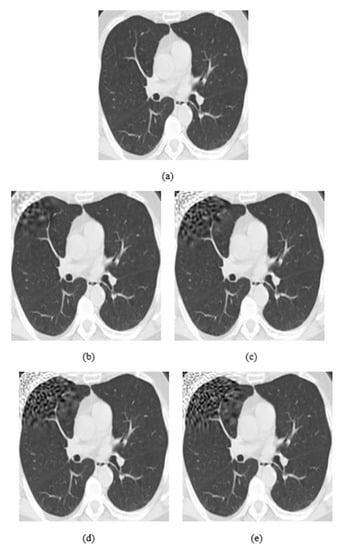

4.2. Ablation Study

The attack consists of three main parameters: embedding strength (a), embedding message length (L-bit), and p values (p1, p2). The embedding strength is an important parameter in digital watermarking because it affects the extraction of information. When the strength value is big, the extraction method is more robust, but the perturbation in images is more visible. The L-bit length concerns the size of information we insert in images. If the size is large, then the part of the image, which is perturbated, is also large. The last parameters, p values (p1, p2), function as coordinates of local patch of the image where the watermark is inserted (Figure 3).

Figure 3.

(a) Watermark embedding with p1 = 0.1 and p2 = 0.1, (b) Watermark embedding with p1 = 0.9 and p2 = 0.9.

As it is shown in Figure 3a, the watermarking is embedded on the upper left corner, as the p parameters are equal to 0.1, while in (b) the watermarking was embedded on the bottom right corner because p values are equal to 0.9. Both p values range from 0.1 to 0.9 by representing all local points of the image. In Figure 4, it is presented how the embedding strength affects the distortion of an image while the other parameters are constant (L-bit = 1000, p1 = 0.1, p2 = 0.1), and in Figure 5 the perturbation is presented from L-bit length (embedding strength = 300, p1 = 0.1, p2 = 0.1). Embedding strength controls the limit of watermark information that is inserted in the image. A large embedding strength provides more robustness, but it is also more perceptible at the same time.